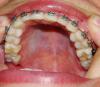

фотографии с прикусом на данный момент времени прикладываю.

post-11949-1315141880_thumb.jpg

post-11949-1315141887_thumb.jpg

post-11949-1315141892_thumb.jpg

post-11949-1315141897_thumb.jpg

post-11949-1315141904_thumb.jpg

post-11949-1315141910_thumb.jpg

post-11949-1315141918_thumb.jpg

post-11949-1315141923_thumb.jpg

post-11949-1315141928_thumb.jpg